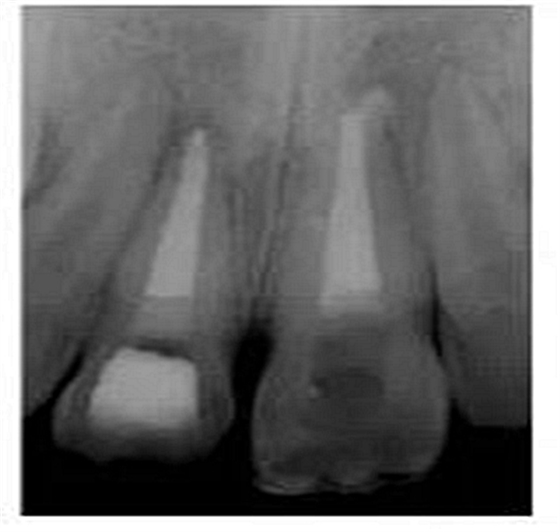

切端則采用透明樹脂,最后使用釉質(zhì)樹脂(Amaris, VOCO, Cuxhaven, Germany)。21的樹脂修復(fù)采用類似的方式。修復(fù)初步成型,拋光,恢復(fù)干燥牙釉質(zhì)的顏色。攝片顯示樁在根管內(nèi)位置合適(圖15)。最后一次復(fù)診精修、拋光充填體,完成治療。